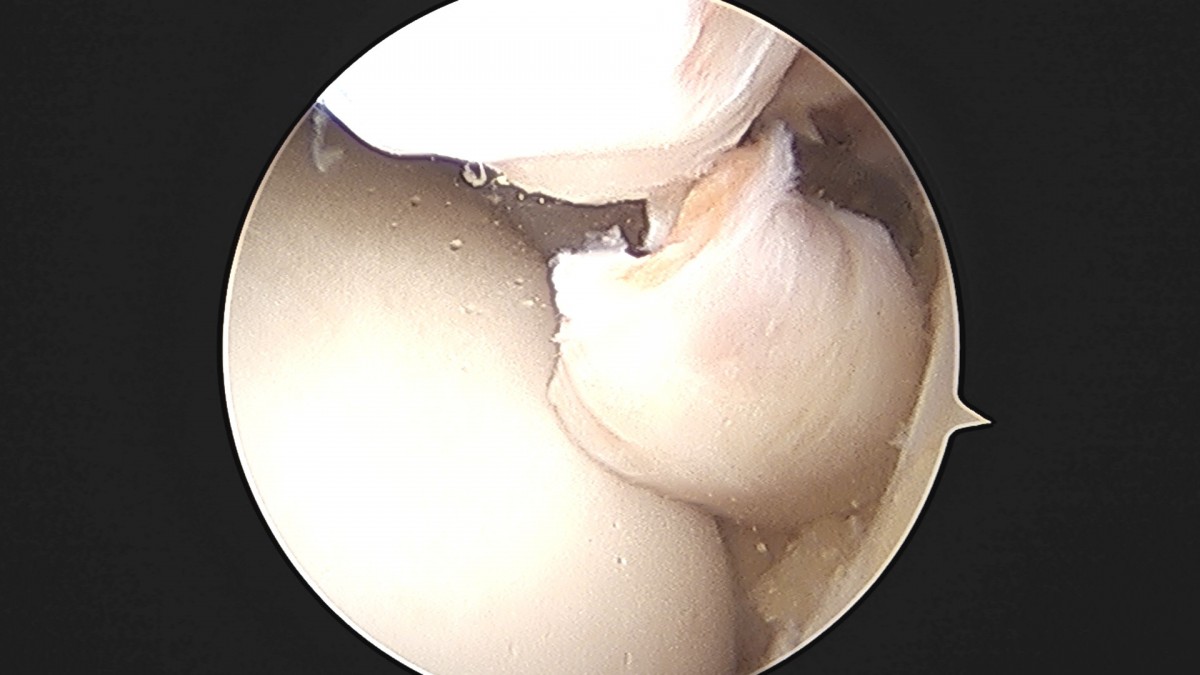

이재상원장님 발목 활액막 절제술 및 인대 봉합술 정보O 환자

dae765e4d9ac96aee867c9d6292d8784_1758003798_3741.jpg